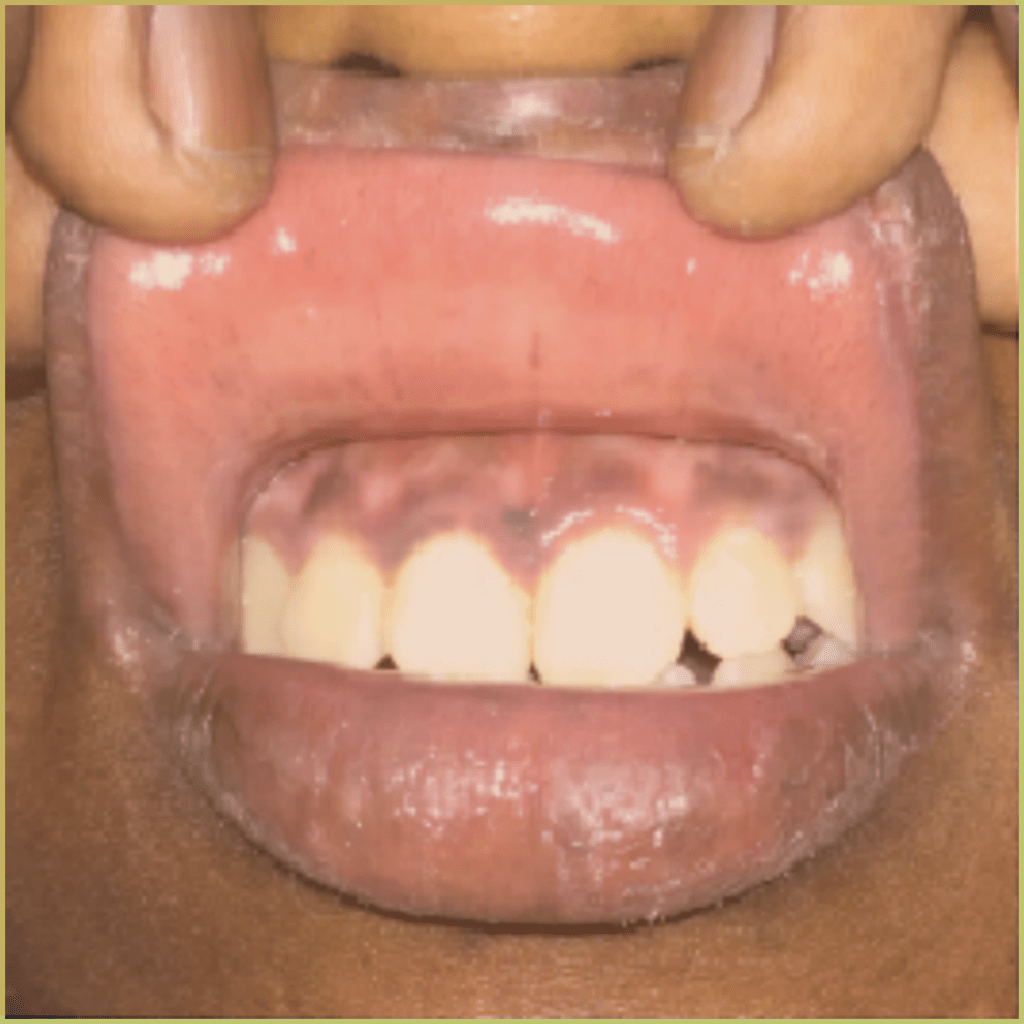

ADDISON'S DISEASE

Addison’s Disease (primary adrenal insufficiency) is a rare autoimmune endocrine disorder that leads to improper steroid hormone production. Recall, cortisol and aldosterone are fabricated in the adrenal cortex. Secondary adrenal insufficiency is caused by decreased production of adrenocorticotropic hormone (pituitary gland) or corticotropin-releasing hormone (hypothalamus). When stressed an inadequate production of adrenal hormones may lead to a potentially serious medical emergency (adrenal crisis). Adrenal insufficiency may also be triggered by infection (tuberculosis, histoplasmosis, coccidioidomycosis), medications (ketoconazole, rifampicin, phenytoin), sepsis, or trauma to the adrenal glands. Visual changes to the skin and oral mucosa are due to secondary melanocyte stimulation by increased levels of adrenocorticotropic hormone (ACTH) or β-lipotropin. The common clinical presentation includes:

- Brown macular pigmentation is usually seen in association with cutaneous bronzing.

- Weakness, weight loss, salt craving, nausea, vomiting, and hypotension.

- May cause behavioral changes (e.g. anxiety, depression, irritability).

Addison’s disease is confirmed using serological testing. Adrenal hormone levels will remain low after stimulation with synthetic ACTH. Diagnosis is based on the lesion history, clinical presentation and microscopic findings, which may include melanosis visible within mucosa biopsy. Your differential diagnosis should include:

- Smoker’s melanosis.

- Normal ethnic pigmentation.

- Heavy metal deposition/argyrosis or amalgam tattoo.

- Drug-induced pigmentation.

- Peutz-Jeghers syndrome.